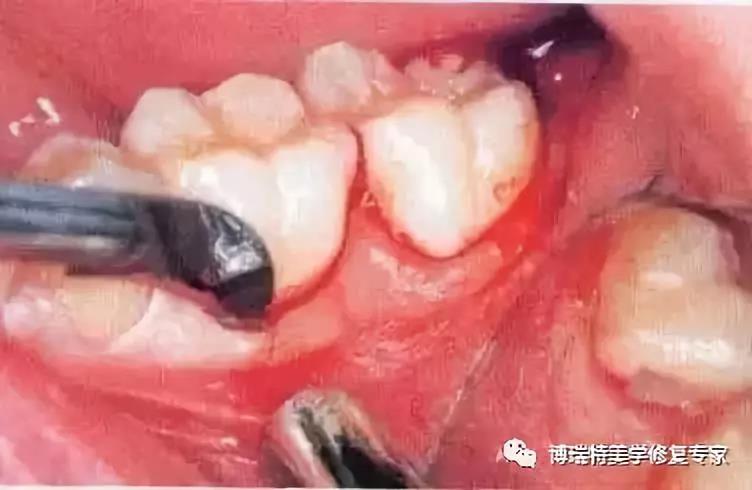

3、翻开黏骨膜瓣显露牙槽嵴。图中已将黏骨膜瓣翻开,在舌侧开窗去骨显露阻生牙的远中颊尖,再通过装在机头上的外科圆钻去除覆盖于(牙合)面的骨质。

4、将牙冠颊侧大部分显露至釉牙骨质界时方能较全面地认识该阻生牙在牙槽窝内的位置。根尖片只能显示该阻生牙在(牙合)面的投影而不能显示其颊舌向倾斜的情况。在低位舌侧近中阻生时,阻生牙同时与邻牙牙根的远中壁和舌侧骨板相接触,故舌侧骨板必然较为薄弱甚至被穿透。(出现骨开窗)

5、由于根分叉较小且较低,第二磨牙牙冠的位置阻碍了车针的正确安放,并且有破坏舌侧骨板的危险。在这种情况下,临床医师从近中颊角开始切割近中部分牙体,这种方法不存在任何风险而且只需要短短的几秒钟。

6、阻生牙仍被远中牙槽嵴所阻挡,故去除远中部分牙冠,使牙顺利向远中颊向脱位。